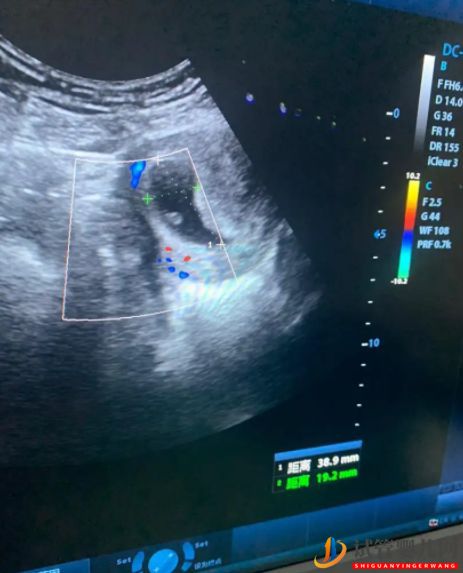

我重點(diǎn)說(shuō)說(shuō)我的經(jīng)驗(yàn)吧,做試管的準(zhǔn)備工作都一樣我就不多說(shuō)了。我總結(jié)了一下主要有以下幾點(diǎn):1.運(yùn)動(dòng)。好的身體是基礎(chǔ),不管你是備孕中還是懷孕中,好的身體素質(zhì)都是我們成功的資本,所以從現(xiàn)在開(kāi)(+Q:914935817)始堅(jiān)持每天運(yùn)動(dòng)吧。2.泡腳。我懷孕前和懷孕中都有堅(jiān)持每天泡腳,包括夏天。只是懷孕的時(shí)候泡的時(shí)間短了而已。3.艾灸。我移植前有做過(guò)艾灸,自己在家里做的。關(guān)于艾灸,我想說(shuō)的是如果你多次移植沒(méi)有成功或者你想一次成功,不妨稍微重視一下這個(gè),畢竟子宮環(huán)境好了,寶寶才愿意在里面安家!4.中藥。我移植前有讓醫(yī)生給我開(kāi)了中藥調(diào)理,我當(dāng)時(shí)的內(nèi)膜長(zhǎng)得還是可以的。然后移植后12天抽血,當(dāng)時(shí)血值800多,醫(yī)生說(shuō)血值可以,讓我回家等第一次B超,也沒(méi)讓查翻倍,我自己不放心,就直接去中醫(yī)院開(kāi)了(+Q:914935817)保胎藥回家吃去了。